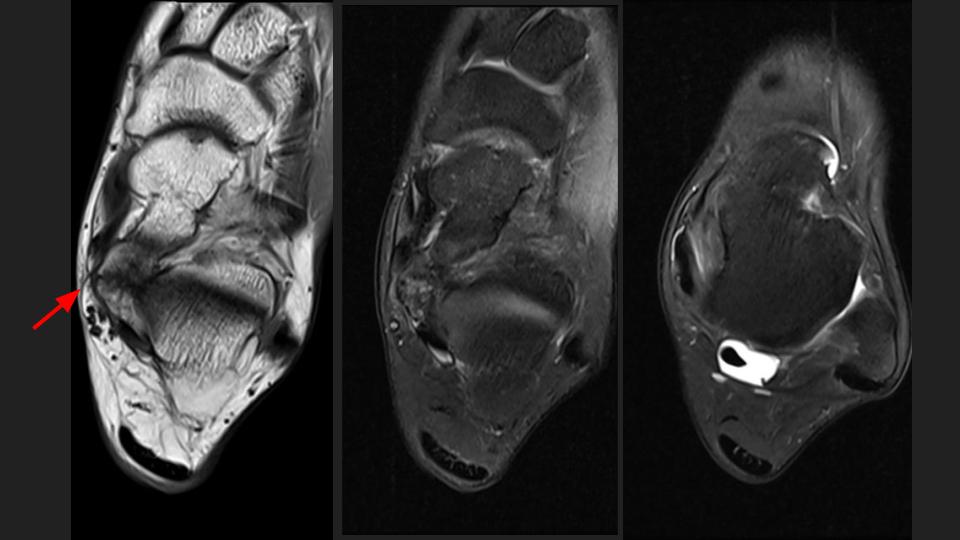

axial.jpeg